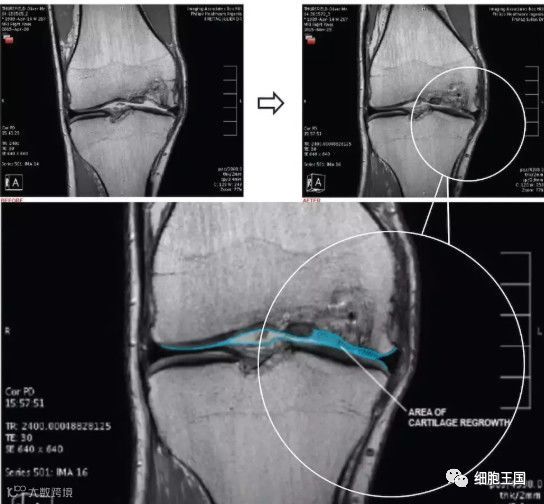

墨尔本干细胞治疗中心利用患者自身的间充质干细胞注入膝关节治疗膝关节损伤的临床研究是全球范围都较为知名的一项临床试验,这个试验共涉及70名患者,分为30名一组进行对照。最终结果显示,大部分参与试验的患者膝关节功能有了很大的改善:三分之二的患者膝盖疼痛程度和活动受限程度减少了一半,并且保持了一年以上。

另一项脂肪干细胞治疗膝骨性关节炎的临床疗效及二期关节镜检查[2]。研究人员分别向30例平均年龄为65岁老年患者的关节腔内注射平均值为4.0 ×106干细胞,随后进行了2年的随访。十六例患者在此期间进行了第二次关节镜检查,几乎所有患者均有明显改善,其中87.5%的老年患者改善或维持软骨状态至少2年。而且,没有一个病人接受过在这2年期间进行全膝关节置换术。

上图a为治疗前关节镜检查结果,可以看出软骨存在缺损。图b为脂肪间充质干细胞联合PRP治疗,图c为治疗后结果,软骨得到了修复。